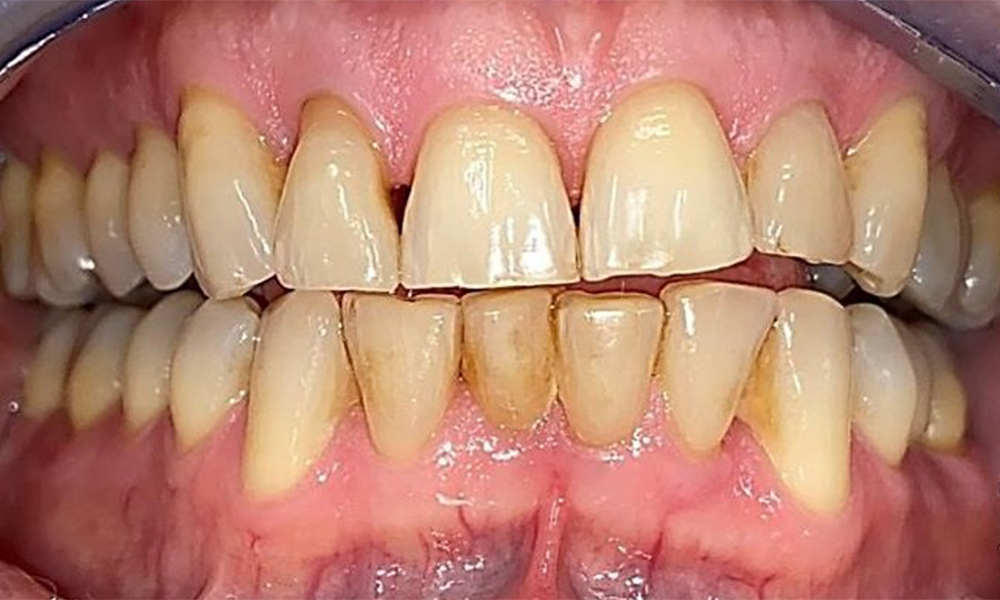

Frontal view with loss of the interdental papillae between 12 and 11.

Fig. 2 Frontal view with loss of the interdental papillae between 12 and 11. © Dr R. Krapf

Right lateral view. Loss of the interdental papillae.

Fig. 3 Right lateral view. Loss of the interdental papillae. © Dr R. Krapf

Left lateral view including the recessions.

Fig. 4 Left lateral view including the recessions. © Dr R. Krapf

The patient has a full dentition with 28 teeth, which includes amalgam and composite fillings in the molar and premolar regions. There is a visible clinical marginal gap present on tooth 14. Tooth 27 has an adequate gold inlay. There are also generalized attritions and abrasions. (Fig. 2, Fig. 3, Fig. 4, Fig. 5, Fig. 6)

Periodontal findings

The patient has stage II, grade B periodontitis (5). At 1 to 3 mm, the clinical probing depths were within the physiological range. Localized probing depths of 5 mm were observed on the mesiopalatal aspects on both 17 and 27. There are generalized recessions of 1–3 mm with partial loss of the interdental papillae (Fig. 2, Fig. 3, Fig. 4)